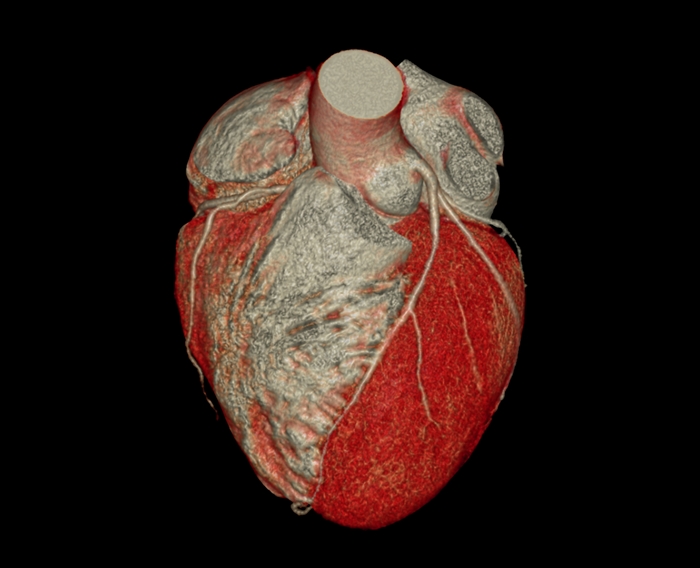

↓こちらも心臓CTで撮影した画像。まるで心臓を取り出したかのような立体的で詳しい画像がとれます。

心臓CT

心臓CTでわかること

冠動脈CTとも呼ばれるように、

狭心症や心筋梗塞の原因となる

冠動脈の動脈硬化をみつける

ことができます。